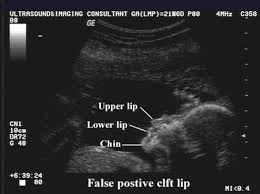

Best seen on coronal images of the upper lip. Type 2 unilateral. My ultrasound tech said that she can easily spot a cleft lip but a cleft palate is much harder to see i am sure you could google ultrasound pics with cleft lips and see some pictures. An explanation why the cleft was mistakenly considered to be one on the left side could be that the cleft was located near to the midline and the 2d ultrasound frontal view was an oblique frontal view figure 1.

Midline sagittal views normal. Ultrasound pic looks like cleft lip and im freaking out. Ultrasound of cleft lip and palate. What does cleft lip look like in ultrasound i think you can see it easily especially the 3d 4d one.

As the fetus continues developing it may be easier to accurately diagnose a cleft lip.